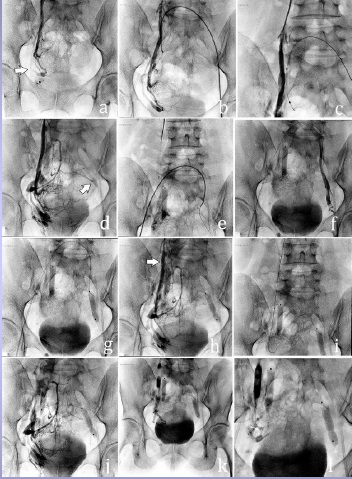

首先对左肾静脉进行导管插入术,如果可能的话,用引导导管(可能是微导管)进一步进行卵巢静脉造影 发现卵巢静脉曲张后,应用栓塞材料进行卵巢静脉栓塞

栓塞后左静脉造影验证疗效,必要的话(可能的干预)右侧和两侧髂内静脉  最少静脉治疗原则,以降低射线剂量